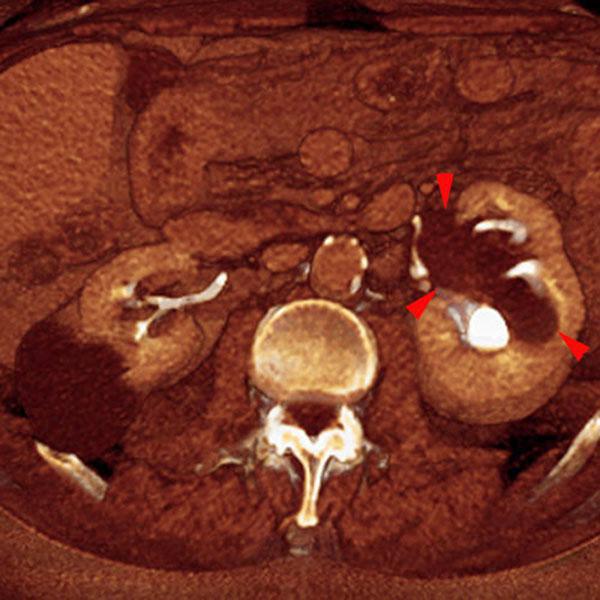

VR seccional. Visión axial caudal. Quistes renales bilaterales. Lesión quística pielosinusal renal izquierda (puntas de flecha) que provoca compresión piélica y dilataciones caliciales